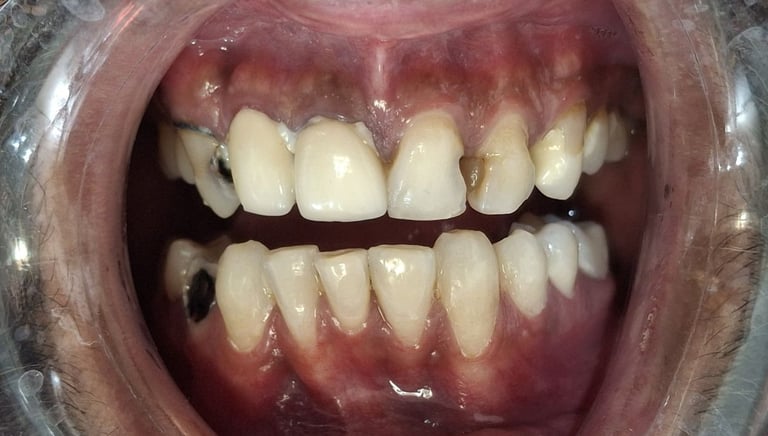

Safe and Effective Teeth Whitening in Shyamal, Ahmedabad

Gentle and professionally supervised teeth whitening designed to safely brighten your natural smile. Our whitening treatment helps remove stains caused by tea, coffee, tobacco, and ageing, giving visible results without harming your teeth. Patients from Shyamal and nearby areas of Ahmedabad choose our clinic for comfortable, controlled, and effective teeth whitening care.

All images shown here are real teeth whitening cases treated at our clinic with patient consent.

Professional teeth whitening helps remove deep stains caused by tea, coffee, tobacco and natural tooth discoloration, resulting in a visibly brighter and more confident smile.

At Shree Dental Care, teeth whitening is performed using safe, clinically approved methods with a focus on comfort, even shade improvement and protection of tooth enamel and gums.

If you are looking for safe and effective teeth whitening in Shyamal, Ahmedabad,you can book an appointment with our clinic.